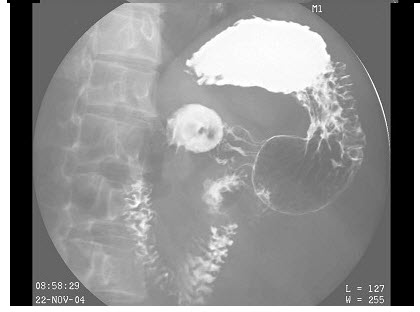

235、单项选择题

膀胱造影片见下图,你考虑什么诊断可能性大()

A.膀胱炎

B.膀胱癌

C.膀胱结石

D.膀胱息肉

E.以上都不是

点击查看答案